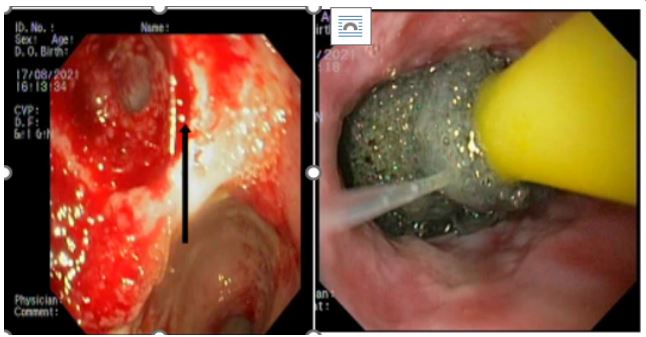

A 59-year-old man has complained of pus and mucus discharge from the anal region, as well as intermittent fever episodes, for the past two years. Three years ago, he developed symptoms of per rectal bleeding and was diagnosed with Carcinoma rectum, for which he received three cycles of neoadjuvant radiotherapy followed by laparoscopic anterior resection with a defuncting descending colostomy. He was discharged on post-operative day 8, with no issues reported. Adjuvant Chemotherapy was administered in 13 cycles. After 6 months of surgery, a CT abdomen was performed, which showed post-op changes in the pelvis with Pelvic peritoneal fat stranding and widening of the presacral space. He was having repeated episodes of fever with chills and pus discharge per anus that were resolved with IV antibiotics. After 6 months, an MRI of the pelvis revealed a significant collection of size 9.1 x 5.2 x 8.8 cm with air loculi at the presacral area-most likely a controlled leak (Figure 2). The conservative approach was continued for another six weeks, during which an intermittent fever with mucus and pus discharge from the anal region persisted. A colonoscopy was performed, which showed the cavity and confirmed the findings (Figure 4). Endovac sponges were sutured to RT and placed directly into the cavity with the help of a colonoscope after debriding and irrigating the cavity. After applying post-E-VAC therapy, the patient improved and had no fever after 48 hours. The procedure was repeated on an OPD basis four more times, with the endovac in place for five days each. At each session of endoscopy, there was a reduction in the size of the sponge used and considerable improvement in terms of the size of the cavity and the amount of slough (Figure 5). The cavity completely healed 10 weeks after E-VAC therapy, and the patient has been asymptomatic for the past 4 months. A CT scan showed complete resolution of the leak.

A 31-year-old female patient with a Bochdalek hernia with complete stomach migration into the left pleural space and ischaemia. Intraoperatively, after bringing down the stomach, the proximal half was found to be gangrenous with perforation. Upper partial gastrectomy and esophagogastric anastomosis were performed. The surviving stomach was oedematous and ischemic, but not gangrenous. A CT scan with intravenous contrast 48 hours later revealed a severely ischemic stomach, raising concerns about its viability. A recheck laparotomy to test the stomach remnant revealed considerable edoema but looked viable. The anastomotic site looks healthy. On the 12th postoperative day, an oral contrast study revealed a frank leak from the anastomosis, with the infected collection tracking up to the left perinephric space, with endoscopy confirming the results (Figure 6). At this point, management options were limited. The covered stent and reoperation were deemed risky. Endoscopic Vacuum (E-VAC) therapy was considered a safe choice in these conditions.

A UGI endoscopy performed to prepare for the endovac revealed a partial breakdown of the anastomosis with a defect size of 3 cm and a subdiaphragmatic cavity filled with slough. The cavity was entered with a scope, and de-sloughing was accomplished with a brush. Normal saline was used to irrigate the cavity. Endovac was used. Forty-eight hours after beginning endovac therapy, there was a significant decrease in SIRS response as measured by fever, pulse rate, WBC count, and CRP. Endovac was done twice more at 5-day intervals. The therapy lasted two weeks in total. At each endoscopic session, the size of the sponge used was reduced, and the cavity size and amount of slough were significantly improved (Figure 7). After 2 weeks of endovac therapy, a CT oral contrast study revealed a significant reduction in cavity size with a well-formed fistula that closed in about 8 weeks. Endoscopies were performed at 3 and 6 months. Both were normal, and the patient is currently on a complete oral diet.

Figure 4: Colonoscopy showing post operative leak after anterior resection of ca rectum and placement of EVAC.

Figure 6: Post operative anastamotic site leak in stomach and placement of E Vac sponge.